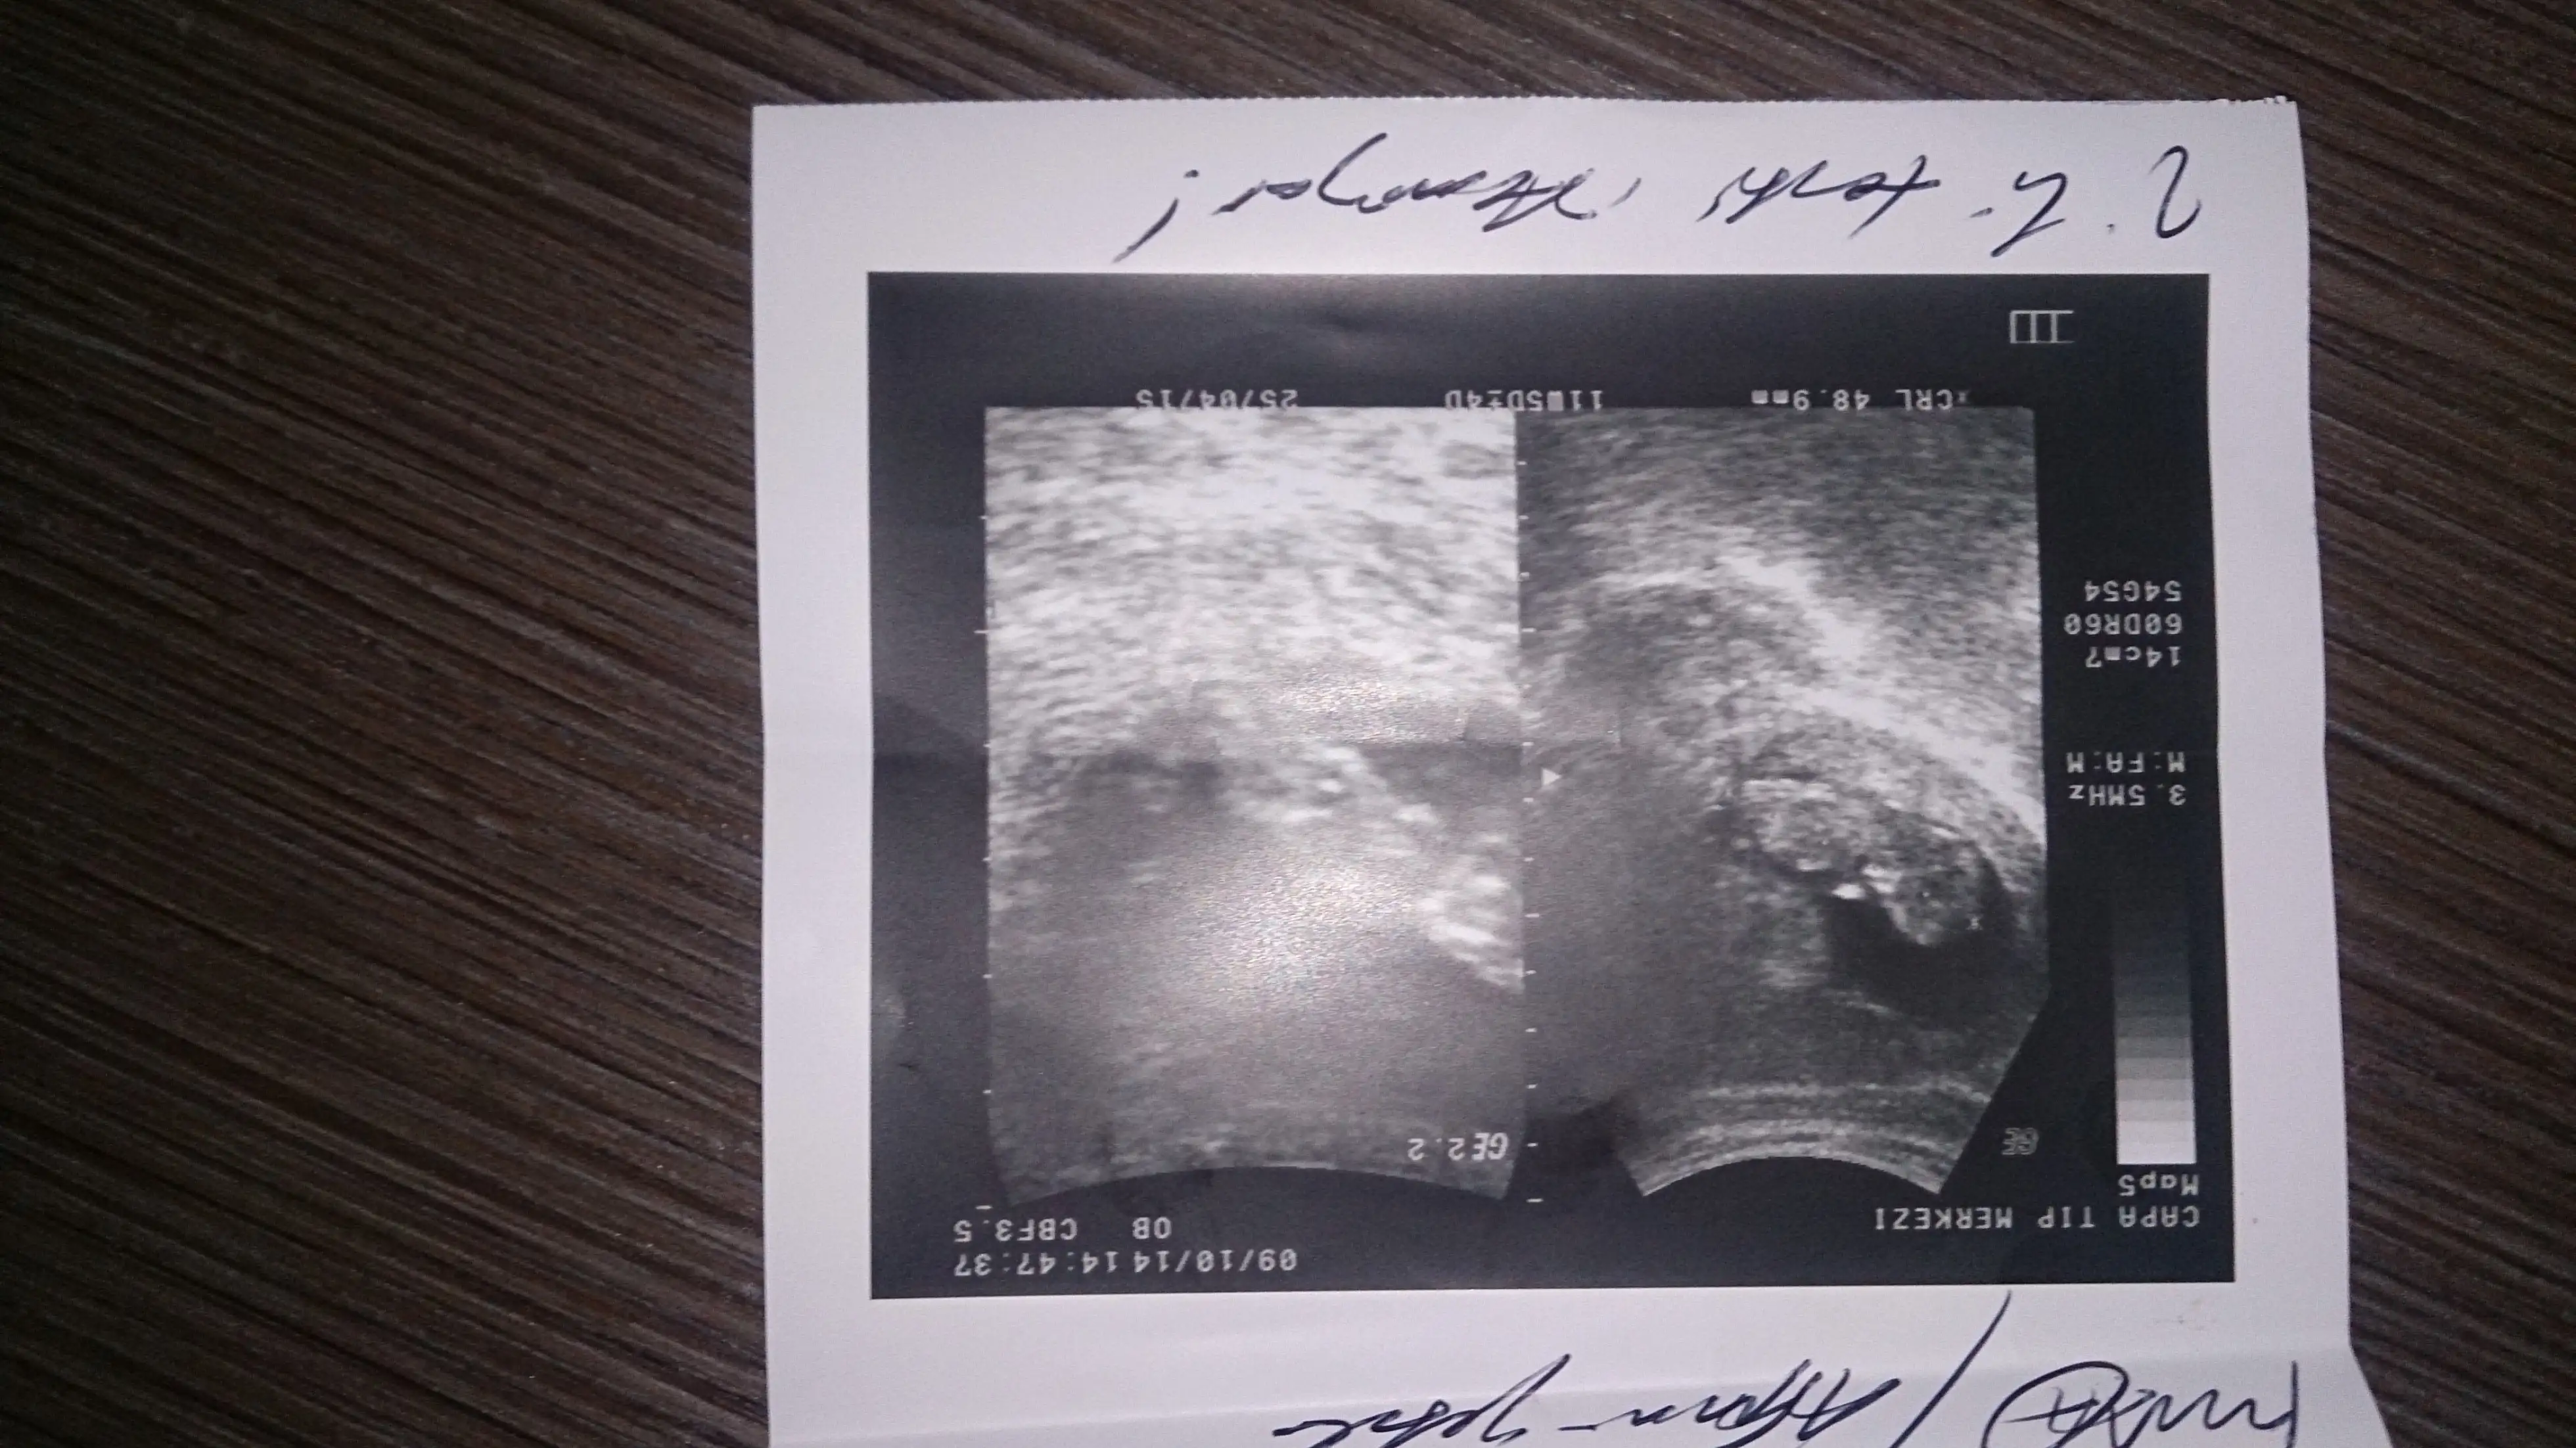

Ayy insallah tesk ederim canimBen bi tahmin yuruteyim nun popoya paralel gibi geldi kiz sanirim...

Efsax seninki baya kesin canm oglus

KizbenceAyy dayanamadim bi foto daha yukledim..))